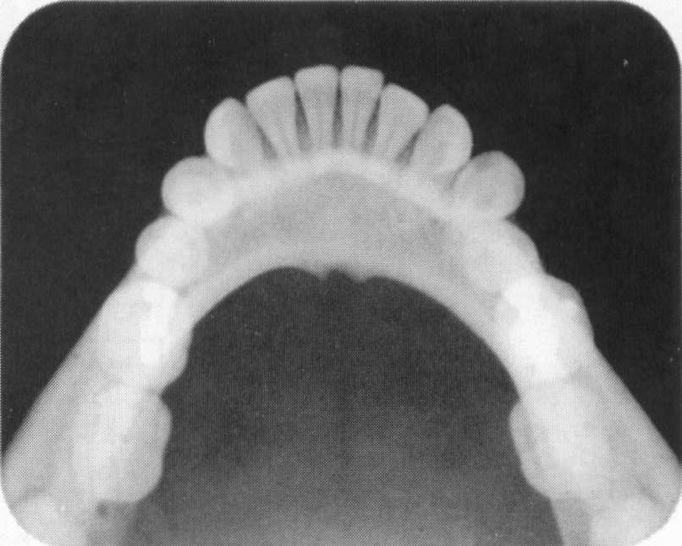

Cross-sectional Technique

yields more information about tori, impactions, and malpositioned teeth. It will also show calcifications in soft tissues, ie. Salivary gland stones or calcifying cysts.

Cross-Sectional Radiograph